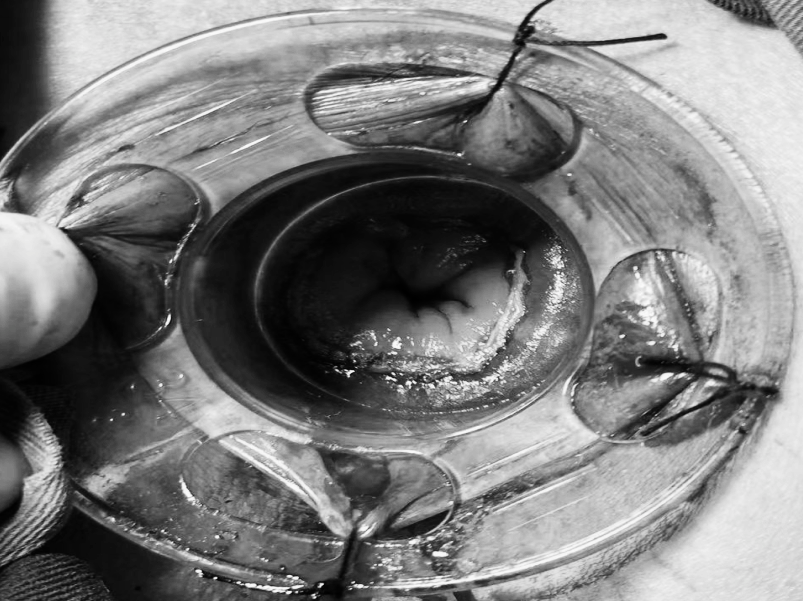

为更好地服务广大患者,贵州航天医院知名肛肠外科专家高大勇教授,每周二上午将固定坐诊贵州航天医院普外科。 坐诊信息 时 间:每周二上午(8:00-11:30) 地 点:贵州航天医院门诊部106诊室(普外科门诊) 挂号通道: 1.门诊大厅或诊室自助挂号缴费机。 2.门诊挂号缴费窗口。 3.贵州航天医院微信公众号预约挂号。 专家简介 高大勇 普外科(肛肠外科)学科带头人、名誉主任,主任医师、教授 临床擅长:对中西医结合诊治肛肠学科各种常见病、多发病及疑难杂症等具有丰富的临床经验。 原遵义市第一人民医院(遵义医科大学第三附属医院)、遵义市中医院肛肠科主任。中华中医药学会肛肠分会常委,全国中医肛肠学科名专家,中国健康促进与教育协会肛肠分会常委,中国康复医学会肛肠疾病康复专业委员会常委,中国民间中医医药研究开发协会肛肠分会副秘书长,中国医师协会中西医结合肛肠医师专业委员会常委,国家二级心理咨询师,贵州省第一批中医名医工作指导老师,遵义市名中医,遵义市肛肠学会会长,遵义市肛肠质控中心名誉主任,遵义市中西医结合学会名誉会长,遵义市健康科普专家,原贵州省中西医结合学会肛肠分会副主任委员、贵州省中医肛肠质控中心副主任、遵义市医学会医疗鉴定委员会专家、遵义市卫生系列高评委。发表论文30余篇,主编和参编医学著作5本,主持省级科研课题2项、市级科研课题2项、院级科研课题1项。 贵州航天医院 普外科简介 基本情况 贵州航天医院普外科成立于1968年,前身属于航天部O61基地3417医院外一科,1998年3417医院、3427医院合并后更名为普外科,下设胃肠外科、肛肠外科2个亚专业科室,拥有在全市较为先进的专科设备和技术,是中国疝病专科联盟单位,贵州医科大学附属医院胃肠外科专科联盟单位。开放床位40张,配备医护人员21人。 专科特色技术 普外科致力于胃肠及肛肠疾病的外科临床诊治及科研,以腹腔镜微创外科技术为本,形成以快速康复治疗胃肿瘤、结直肠肿瘤、小肠肿瘤、直肠脱垂、肥胖病、急腹症、各类疝、痔、瘘等专科特色,同时注重胃肠疾病尤其是结直肠恶性肿瘤的基础研究和临床转化研究,总体诊断和治疗水平在区域同级医院居于领先水平。 开展手术:腹腔镜下胃癌根治术,腹腔镜下袖状胃切除术,腹腔镜下胃肠道间质瘤切除术,腹腔镜下结、直肠癌根治术,胃癌、结直肠癌的精准治疗,腹腔镜下小儿疝气、成人疝修补术,腹腔镜下阑尾手术,内痔的硬化注射治疗及痔疮的微创治疗:ATH、PPH、TST,直肠脱垂的各种手术治疗,难治性伤口VSD技术,鼻胃肠管、肠梗阻导管置入术,肛肠术后间歇性导尿技术,并引进了中医适宜技术,也为各种化疗患者提供输液港安装,提高患者就医体验。 腹腔镜下腹股沟疝 无张力修补术 腹股沟疝里金斯坦(Lichtenstein)手术 PPH微创术治疗环状混合痔 黏连性或炎性肠梗阻-肠梗阻导管 腹腔镜袖状胃切除 腹腔镜阑尾切除术 腹腔镜阑尾肿瘤切除术 腹腔镜下结肠癌根治术 科室诊疗范围 胃肿瘤、结直肠肿瘤、小肠肿瘤、肥胖症、各类急腹症、腹部外伤、腹壁疝、便秘、直肠脱垂、痔疮、肛瘘、肛裂等胃肠、肛肠外科疾病。 END